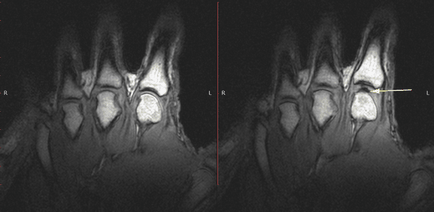

Kanadai kutatók mágneses rezonancia képalkotás tudtak válaszolni a kérdésre, hogy miért a válság akkor hallható, amikor húzza az ujját. Ez alkalommal, a tudósok által vezetett professzor Gregory Kovchuka (Gregory N. Kawchuk) Universtita az Alberta vették igénybe a technológia fejlődése a XXI században. Ők építették olyan eszköz, amely lehetővé teszi, hogy húzza az ujját egy időben részeként a kéz volt a tomográf. Tomográf folyamatot rögzített ütemben 3,2 másodpercenként.

És az ok gyorsan képződnek az ízületi üregbe. A munka címe tanulmány ( „Pull my finger”) tükrözi a lényeg -, hogy folyik a megfigyelés, amit felvett segítségével MRI és megmutatja, mi történik belül az ízületek.

teszt ujjait felváltva helyezzük cső csatlakozik a kábel, ami egy kicsit húzta a válság a közös. Crunch rögzített MRI valós időben, és történt minden 310 milliszekundum.